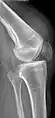

Quadriceps tendon rupture in plain X-ray

Quadriceps tendon rupture in plain X-ray: Incomplete rupture with haematoma in tendon.